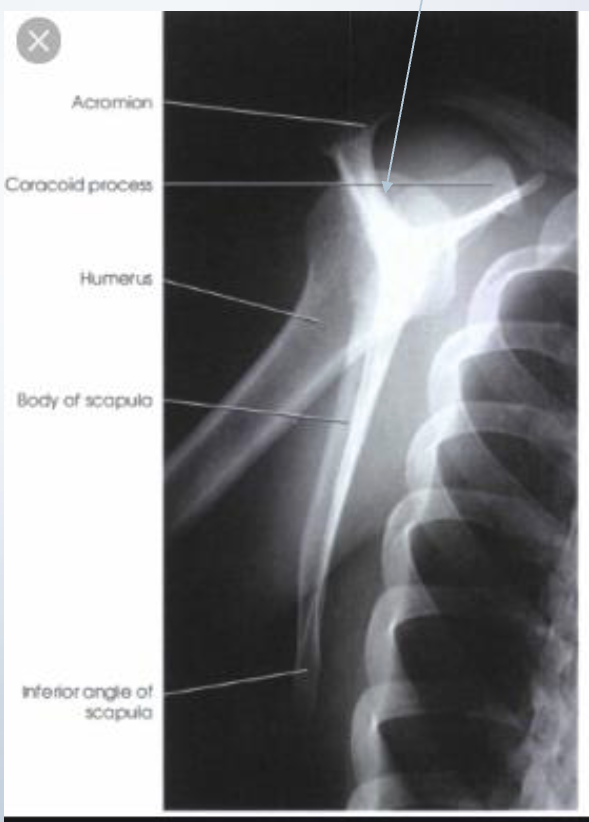

Label the joints

Acromioclavicular (AC)

Scapulohumeral

Sternoclavicular (SC)